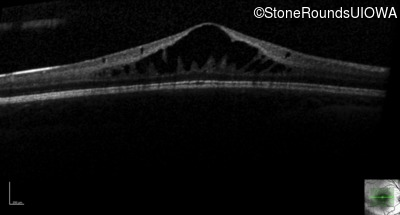

This 6 year old boy first experienced difficulty reading and seeing the blackboard at age 5.

| Age at visit: 6 years |

| Age at visit: 11 years |

| Age at visit: 14 years |

| Age at visit: 14 years (Visit 2) |